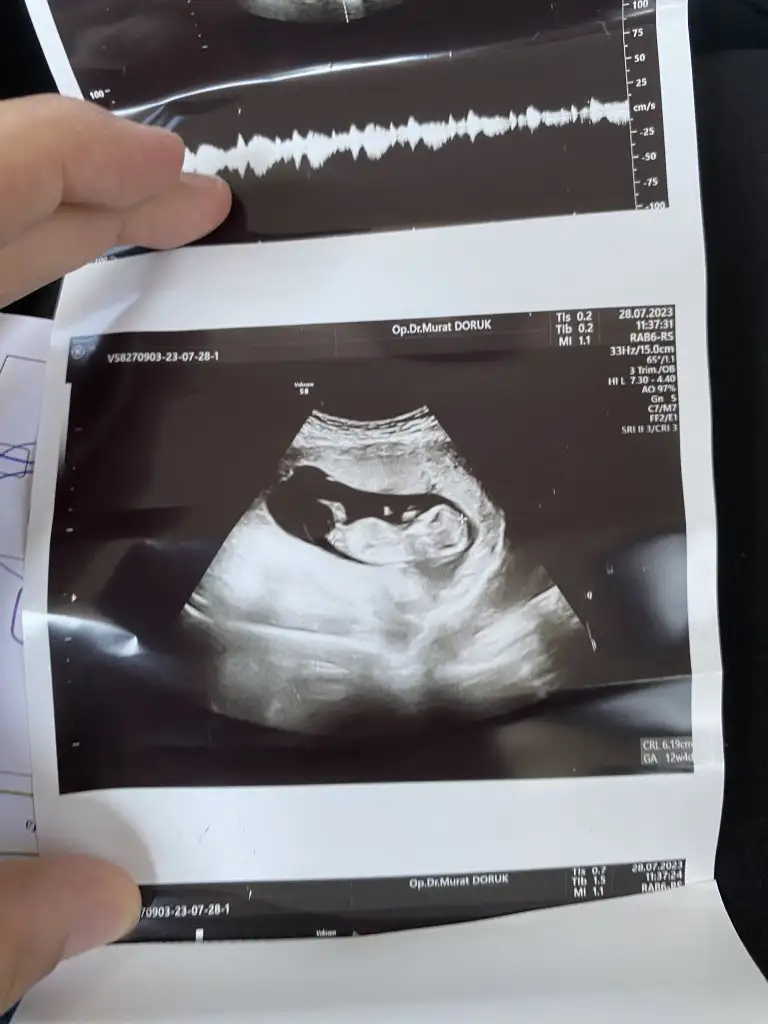

iyi maşallahYaptırdım12 haftalıkken gidicektim ama dayanamadım tam 11 olduğumda gittim ultrasonda 11+4 çıktı ense kalınlığı burun kemiği bakıldı normal çok şükür kan sonucum daha çıkmadı 1inde cikicak

Rabbim Sağlıkla kucağınıza almayı nasip etsin bende bugün kontrole gittim ancak cinsiyet söylemedi genel kontroldu çok şükür kanamamda bitti bebekte çok iyi hareketli